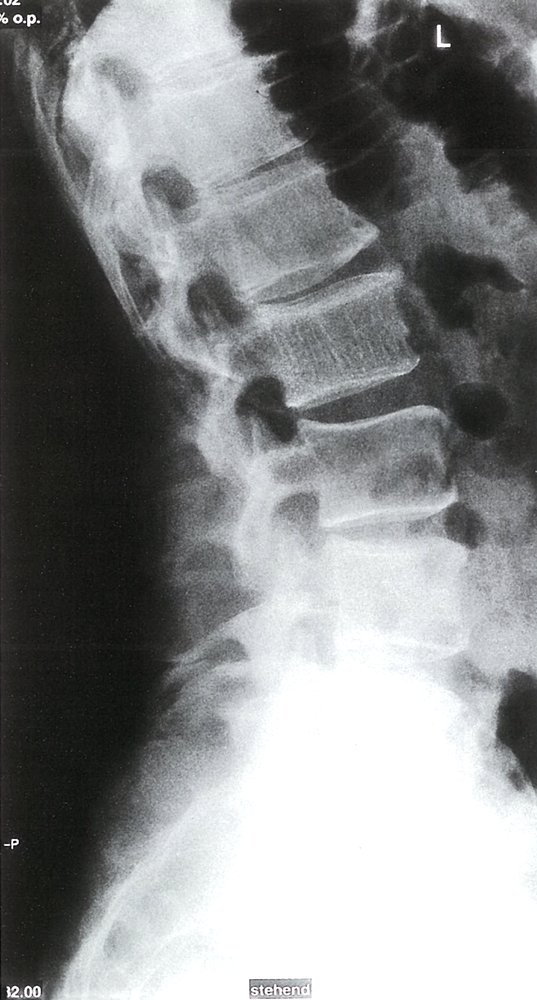

• Description: vascular neoplasm [10]

• Epidemiology

• Peak incidence: 30–50 years

• Sex: ♂ < ♀ (1:2)

• Clinical features

• Most common benign tumor of the spine, particularly in the thoracic and lumbar vertebrae

• Usually asymptomatic; often an incidental finding

• Diagnostics: x-ray

• Vertical streaks visible in vertebrae

• Honeycomb appearance of lesion with sharp margins

• Treatment: usually no treatment required

• Complications

• Compression fractures

• Spinal stenosis

• Bleeding with subsequent spinal epidural hematoma